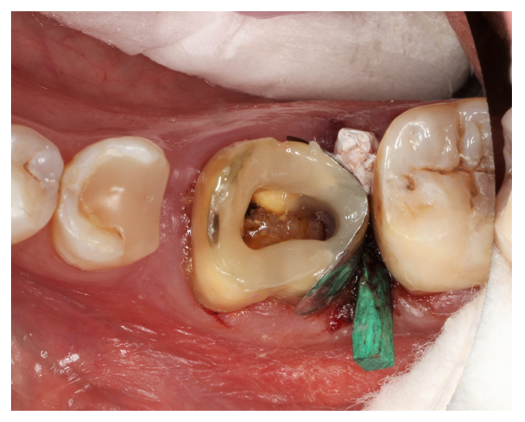

Darstellung der Restauration von Wurzelkaries 36 distal am Kronenrand und 37 mesial bei einem 82-jährigen Patienten. Röntgenologisch sind tiefe, pulpanahe Defekte sowie ein deutlicher interdentaler Knochenabbau sichtbar (Abb. 1), klinisch zeigte sich eine negative Sensibilität beider Zähne. Der Patient war zum Zeitpunkt der Vorstellung beschwerdefrei, die Zähne zeigten keine Lockerungsgrade.

Abb. 1: ZF Regio 36/37 mit ausgeprägter pulpanaher Wurzelkaries und deutlichem interdentalen Knochenabbau | Foto: Anne-Katrin Lührs

Als vorbereitende Maßnahme vor der endodontischen Intervention erfolgte zunächst die Restauration der kariösen Läsionen, die aufgrund der deutlich subgingivalen Lokalisation herausfordernd war. Durch die notwendige Entfernung der Krone an Zahn 36 konnte zunächst die Läsion an 37 adhäsiv restauriert werden, da sie jetzt deutlich besser zugänglich war. Anschließend erfolgte die präendodontische Restauration des Zahnes 36. Nach Anlage einer Teilmatrize mit zervikaler Lasche (Abb. 2) erfolgte die zusätzliche Abdichtung mit Teflonband (Abb. 3).

Abb. 2: Teilmatrize mit großer vertikaler Höhe durch die vorhandene zervikale Lasche | Foto: Anne-Katrin Lührs

Der Keil wurde nur vorsichtig nach interdental eingebracht, um die Matrize nicht zu verformen. Die Separation konnte anschließend durch Anlage eines Separationsringes erreicht werden. Da eine Kofferdamisolation nicht möglich war, wurde der Ring zusätzlich mit Zahnseide gesichert.

Abb. 3: Isolation des deutlich subgingivalen Defektes an Zahn 36 nach Kariesexkavation. Neben einer federharten Teilmatrize mit subgingivaler Lasche wurden Teflonband, ein interdentalkeil sowie ein mit Zahnseide gesicherter Separationsring zur Kontaminationskontrolle eingesetzt. | Foto: Anne-Katrin Lührs